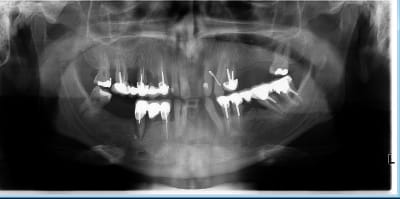

patient de 40 ans, pas d ATCD, ne fume pas.

Paro +++

bridge sect 1 cassé, avec mobilité ++ sur 15 et

mobilité +++ sur 22 24 et plus modérée au niveaudu bridge sect 3

Quelles dents serait il possible de conserver ?